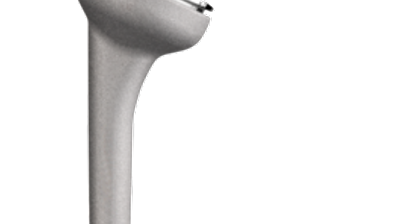

Rotatorenmanschettenruptur

Als Rotatorenmanschette wird jene Muskelgruppe bezeichnet, welche sich zwischen dem Schulterblatt (Scapula) und dem Oberarmkopf (Caput humeri) erstreckt und wie eine Muskelhaube den Großteil des Oberarmkopfes umschließt. Eine intakte Rotatorenmanschette gewährleistet durch das funkt...